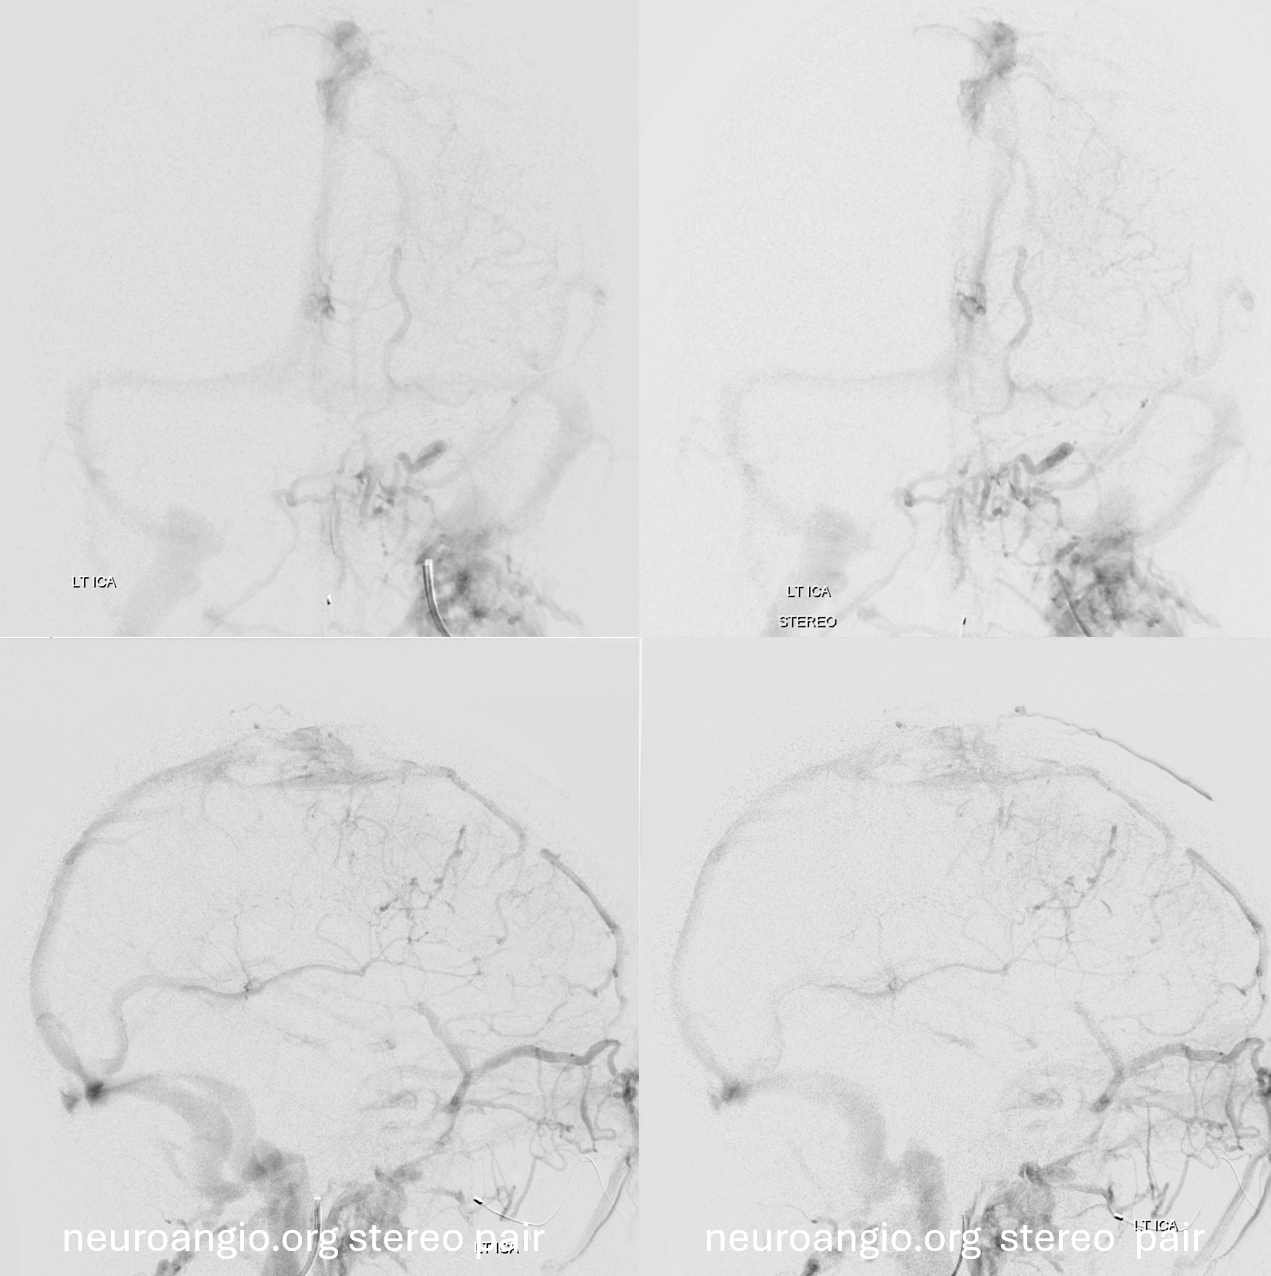

Later on… right side is good

Left side is bad — can you see it?

Later phase of bad